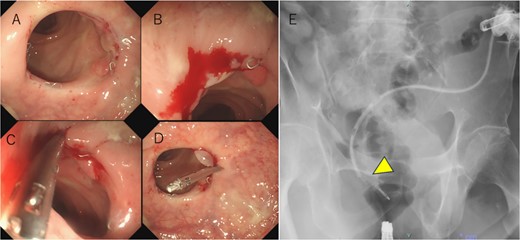

Following reoperation, although drainage led to shrinkage of the fistula, it persisted after 2 months (Fig. 2). Hence, we decided to close the fistula using endoscopic clips. Gastrografin was injected through the drain under colonoscopy and radiography, and bleeding was observed at the suspected fistula orifice, which was provisionally clipped using a MANTIS clip. Gastrografin was injected again, and definitive clipping was completed confirming the successful fistula closure (Fig. 3). The patient was discharged after 2 days. The drain was withdrawn about 3 cm on day 9 after discharge. On day 15, gastrografin injection under radiography revealed recovery of the fistula (Fig. 4). Thereafter, the drain was withdrawn cautiously about 2 cm every 2–3 days to prevent residual fistula formation and removed completely on day 29. Ileostomy closure was performed 6 months after the initial surgery. The patient was discharged without complications on postoperative day 7.

(a) Hyperplastic granulation tissue around the right side of the anastomosis. (b) Minor bleeding is observed after the gastrografin is injected through the drain. (c) A suspected fistula orifice site is closed provisionally using a MANTIS clip. (d, e) After provisional closure of the fistula orifice with a MANTIS clip, gastrografin is injected again through the drain, and no anastomotic leakage is observed (arrowhead). Subsequently, a definitive clipping is performed.